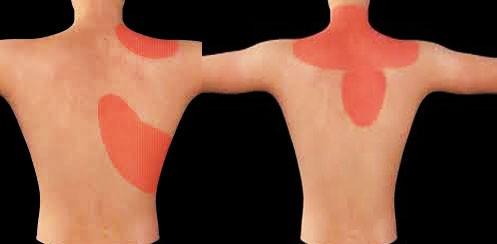

之所以把心梗诱发的肩痛写在最前面,是因为忽视这个问题可能导致非常严重的后果。很多朋友可能都知道发生心脏缺血、甚至心梗的时候,会有严重的胸痛,有的会伴有呼吸困难,大汗淋漓以及濒死感,但是可能有一些朋友比较忽略的是心肌梗死可能造成的症状就是肩膀疼痛、胃痛、牙痛和肩胛骨区域的疼痛。

尤其是一些患者,如果平时肩膀就不是特别的好,那么在发生心梗的时候,如果出现了肩膀的疼痛,可能就会因为平时有肩痛的毛病而忽视考虑存在心梗的可能,所以建议,有常年的高血压、冠心病、糖尿病的患者,又或者平时频繁的出现心绞痛,又或者最近特别的劳累,长时间的处于高压状态下,出现了肩膀的疼痛、胃区的不适、或者是牙周的疼痛,如果经过15~30分钟不缓解,甚至有越来越重的情况,很有可能是心肌在求救,请一定要考虑到有可能是心肌梗死,无论年纪多大,因为现在出现猝死的年龄段越来越年轻化了。

胆囊疾病可能导致肩膀的疼痛。

但有一部分的患者不仅表现为肝区、胆囊区的不适,还会表现为肩膀和背部的不适。

由胆囊诱发的肩部疼痛,往往有它的特点,如果是慢性胆囊炎症,往往疼痛并不是特别的严重,而且一般都是在进食比较油腻的食物以后出现疼痛。因为在进食大量脂肪的时候,胆囊会分泌胆汁刺激到胆囊,诱发疼痛。发生急性胆囊炎或者是因为急性的胆管梗阻造成胆道问题的时候,患者不仅会表现为疼痛,同时会表现为恶心,腹痛等症状,严重的患者甚至会出现发热、皮肤黄疸,所以由胆囊诱发的疼痛和肩关节疾病导致的疼痛还是有一些可以鉴别的地方。另外如果存在胆囊的炎症或者是胆石症,可以通过彩超检查来明确胆囊是否存在着问题。